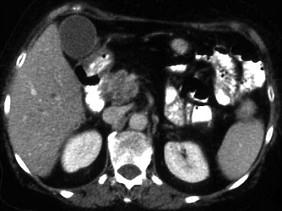

问题 胰头癌最主要的临床表现是 ( )

选项 A、消瘦和乏力 B、黄疸 C、食欲不振和消化不良 D、消化道梗阻 E、上腹疼痛 单选题

答案 B